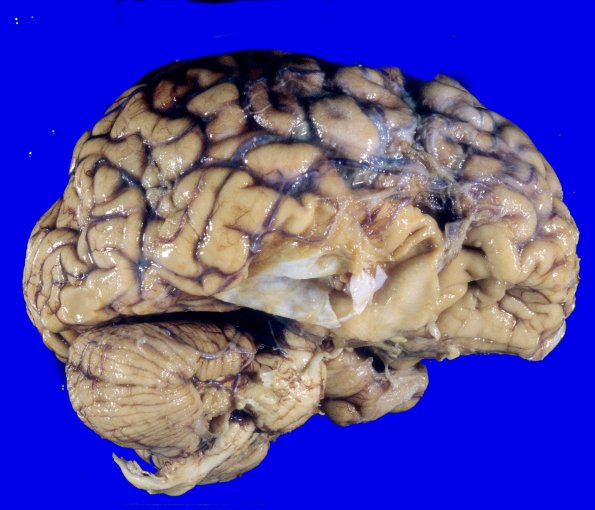

This lateral view of the right cerebral hemisphere shows disruption of the temporal lobe which is overlaid by a thickened membrane which was separate from the dura mater.